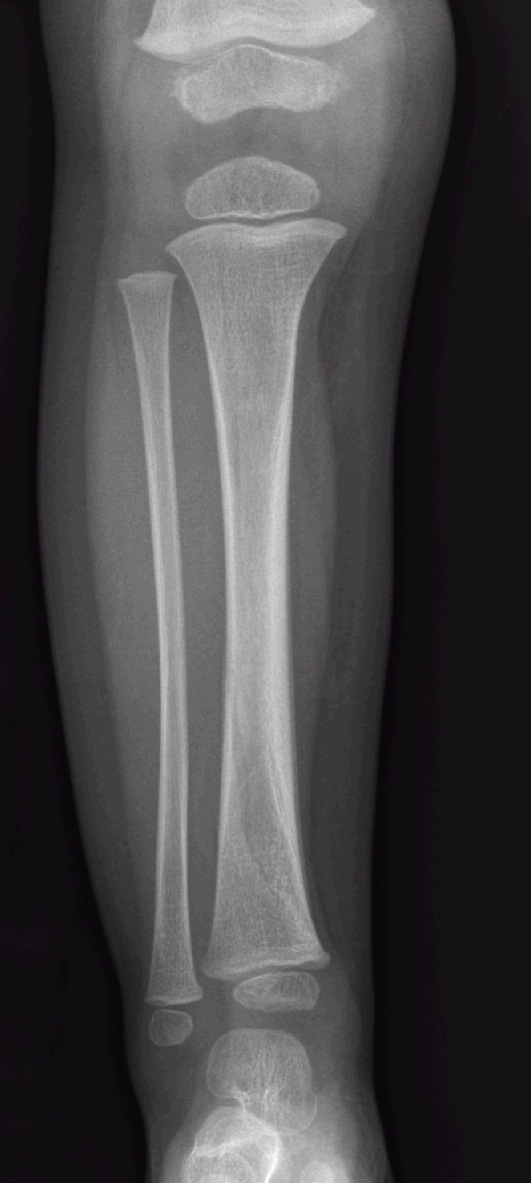

A 2 yo male presents refusing to bear weight on his right leg. There is no known trauma. Parents report he is very active and playful with older siblings. He has focal tenderness over the distal tibia. No fever and no pain with range of motion at the hip. What's the diagnosis? (scroll down for answer)

Answer: Toddler's Fracture

- Spiral or oblique non-displaced fracture of the distal tibia

- Very common in ambulatory toddlers, occurs with low energy falls or twisting injuries

- Initial radiographs are normal in 13-43% of cases, often a clinical diagnosis